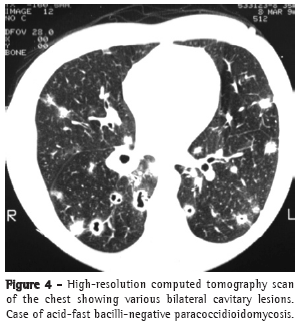

In most cases, the clinical complaints, the physical examination data, and the radiological alterations presented by these patients did not allow a clear distinction to be made between the two diseases in most cases (Figures 2-4).

Pulmonary alterations are typically bilateral, predominantly in the middle lobes and spinal cord regions.(16,17)

In contrast, TB affects males and females of all ages, the majority of whom are symptomatic and present abnormal physical examination findings, as well as radiological alterations, which can also be bilateral but are typically most pronounced in the superior and posterior segments.